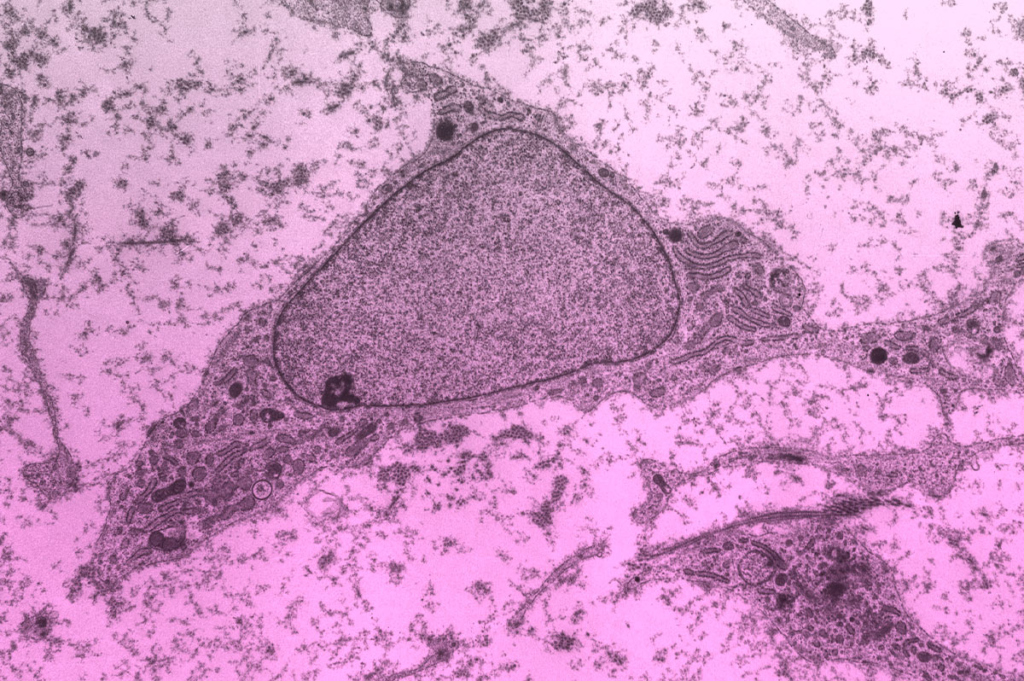

ГСК, или гемоцитобласты, – это предшественники всех клеток крови, находящиеся в основном в костном мозге. Они способны к самоподдержанию и дифференцировке (превращению) в эритроциты, лейкоциты и тромбоциты. ГСК используются для трансплантации при лечении рака крови и иммунных заболеваний.

Это клетки, способные самообновляться и дифференцироваться в различные типы тканей (костную, хрящевую, жировую). Получаемые из костного мозга, жировой ткани и пуповины, они активно применяются в регенеративной медицине и ортопедии, обладая способностью мигрировать в зону повреждения и снижать воспаление.